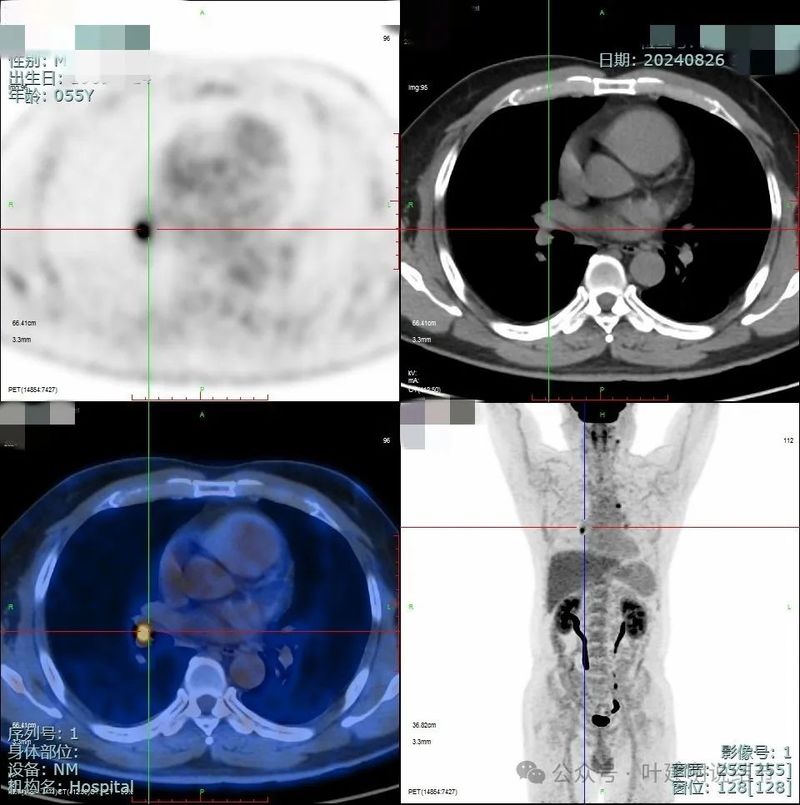

PET-CT检查情况:

PET检查结果示右肺上叶后段小结节,葡萄糖代谢轻度增高,考虑低代谢肿瘤性病变可能性大。